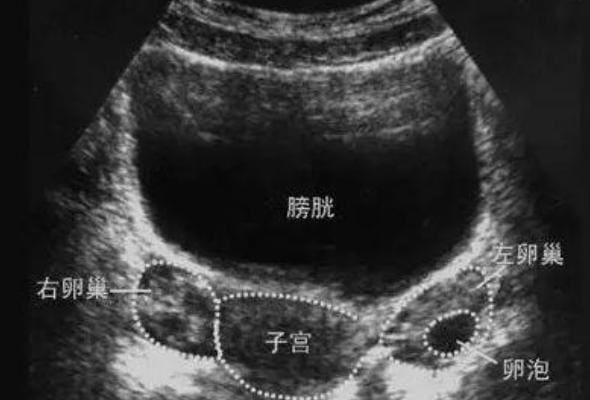

在试管婴儿和代孕过程中,子宫和卵巢的情况决定了能否顺利进入下一步。传统二维超声虽然常用,但在细节上还是有局限。哈萨克斯坦的中心普遍使用三维超声,这就像是从“平面图”升级到“立体模型”,能更全面地呈现子宫结构,发现可能影响胚胎着床的小问题,比如子宫内膜厚度不足、宫腔形态异常等。

同时,多普勒监测在这里用得很普遍,它能检测子宫和卵巢的血流情况。血流越好,说明子宫内膜的接受能力越强,胚胎更容易着床。对于卵巢来说,血供情况也能提示卵泡的质量,这为医生判断取卵时机提供了更科学的依据。